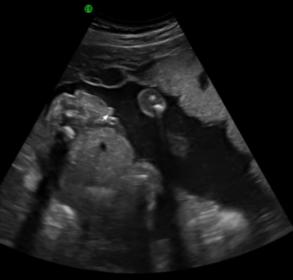

19w6d - gender potty shot

Attachment 7616